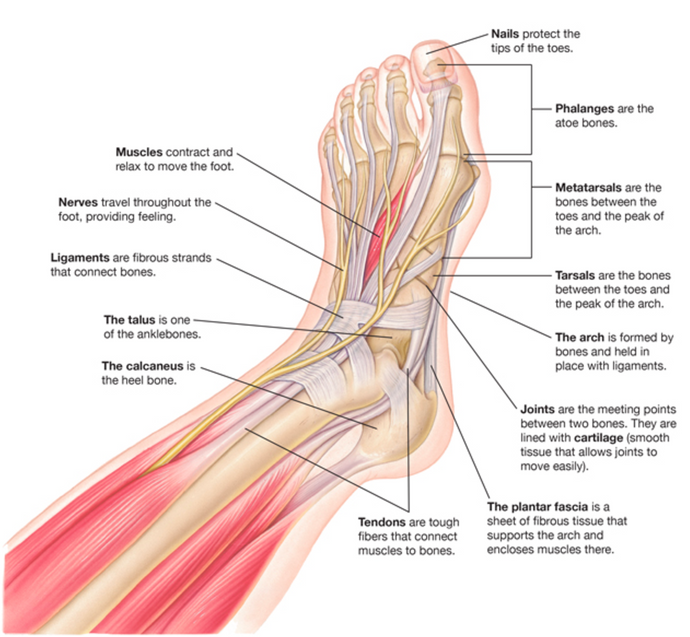

This is the first in a series of posts throughout the year that are meant to help provide you with information to help you care for your feet. We are starting with the basics and will go more in-depth as the year moves along. Future posts will address topics such as muscle care, common foot problems and how to deal with them, how to properly fit shoes, and so much more.

We’d like to investigate if a wide toe box, minimalist shoe can help plantar fasciitis. What is plantar fascia and how does your footwear affect it? Read on to find out!

Take a look at our foot health blog about bunions where we explore causes and treatments of bunions including the health benefits of wide toe box shoes.